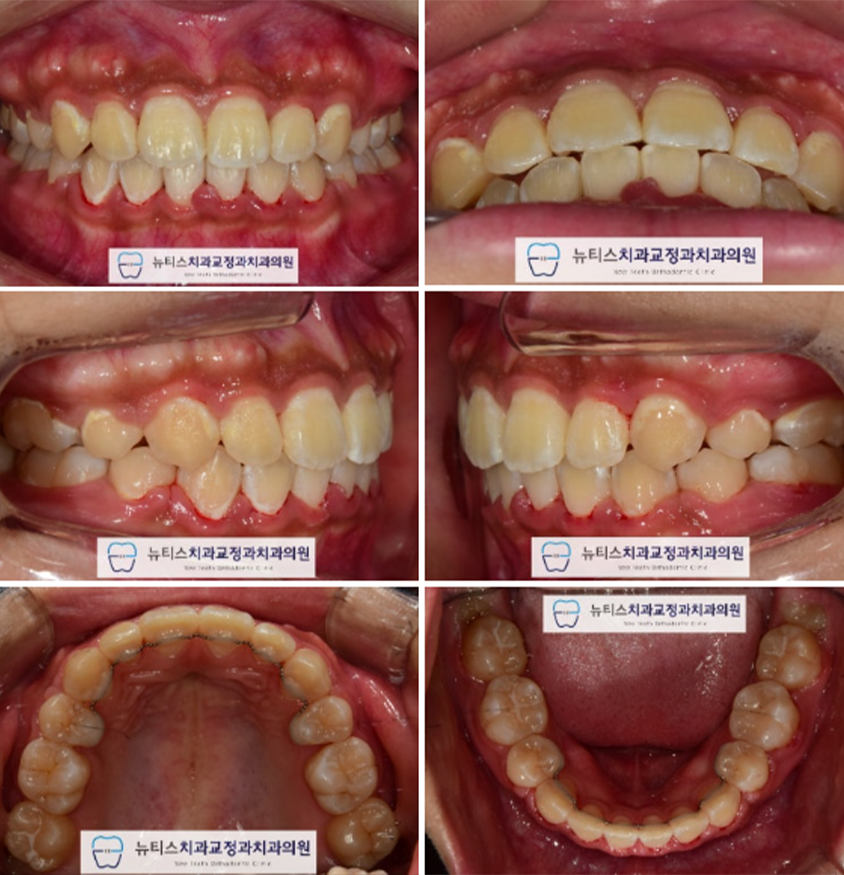

ÀåÄ¡ Á¦°Å ÈÄ »çÁøÀÔ´Ï´Ù.

¾ÕÀ¸·Î »µÃÄÁø Ä¡¾Æ°¡ ÀÌ»Ú°Ô ¹è¿µÇ¾ú½À´Ï´Ù.

¶ÇÇÑ ÃÊÁø ´ç½Ã ¸¹ÀÌ Æ²¾îÁöÁø ¾Ê¾ÒÀ¸³ª

°¡Áö·±ÇÑ Ä¡¿°ú ÇÔ²² ±³ÇÕ°ü°è°¡ ¸ÂÃçÁ³½À´Ï´Ù.

ÀåÄ¡ Á¦°Å ÈÄ ¹æ»ç¼± ¹× Ãø¸ð »çÁøÀÔ´Ï´Ù.

Ãʱ⿡ ºñÇØ °³¼±µÈ ¾Õ´Ï °¢µµ¸¦ È®ÀÎÇÒ ¼ö ÀÖ½À´Ï´Ù.

¶ÇÇÑ ÀÔ¼ú¼±ÀÌ °³¼±µÇ¾úÀ¸¸ç

ÀÚ¿¬½º·¯¿î ÀÔÀÇ ´Ù¹°±â ¹× ¾Æ·¡ÅÎ ¶óÀεµ ¸¹ÀÌ ÁÁ¾ÆÁ³½À´Ï´Ù.

Àü ÈÄ ºñ±³»çÁøÀÔ´Ï´Ù.

¾Õ´Ï °¢µµ°¡ °³¼±µÇ¾ú°í

»ó´ëÀûÀ¸·Î ¹«ÅÎÀÎ ºÎºÐÀÌ ÁÁ¾ÆÁ³½À´Ï´Ù.

ÀÚ¿¬½º·¯¿î ÀÔ¼ú´Ù¹°±â°¡ Çü¼ºµÇ°í

ºÎµå·¯¿î À̼ø±¸°¡ Çü¼ºµÇ¾ú½À´Ï´Ù.